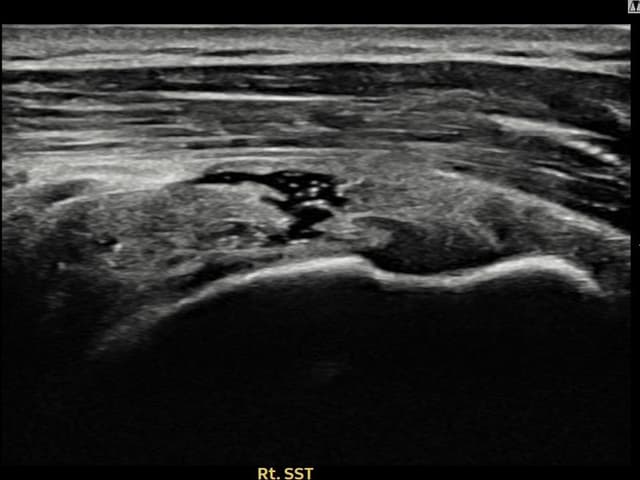

[経過期間: 24.05.15~24.07.23]

[縫縮術] 超音波検査にて右 棘上筋腱 部分断裂 + 건내 석회화(9mm × 4mm (腱厚の約38%欠損))を確認。縫縮術施行後、腱の連続性が回復し、日常生活に復帰されました。